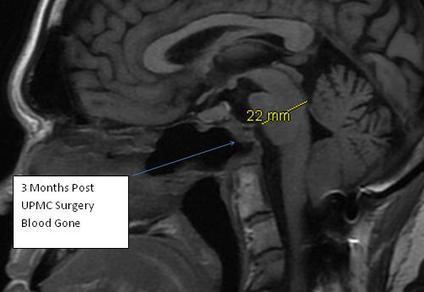

MRI 3 months post surgery -   Blood resolved. Brain stem relaxed and expanded forward by almost 4 mm which might as well be a football field (in places) in the brain for those who are not familiar with brain anatomy.

Physicians at UPMC in Pittsburgh developed new technique around 2010. Using a small endoscope, through the nose, then a small catheter through the back of the nasopharynx ( nose/mouth ) they removed ( via tiny drill ) most of C1 and C2. Quite risky being that close to brain stem. No small complications, sort of an all or nothing thing. This is me 2 weeks post surgery.